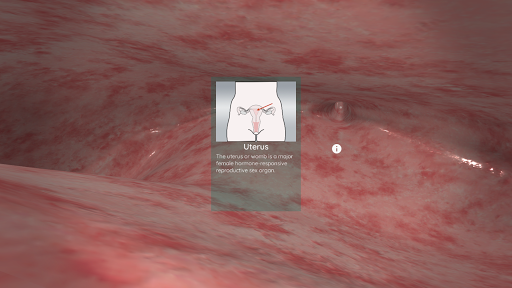

Korzystając z wirtualnej rzeczywistości, będziesz w stanie poruszać się wzdłuż struktur anatomicznych, stając się częścią ludzkiej anatomii: układu rozrodczego układu krążenia, oddechowego, trawiennego, moczowego, łzowego i żeńskiego.

W trybie wirtualnej rzeczywistości urządzenie mobilne (smartfon) musi być umieszczone w gadżecie wirtualnej rzeczywistości, aby cieszyć się w pełni wciągającym doświadczeniem. Użytkownik może wchodzić w interakcję z elementami sterującymi nawigacją i elementami informacji anatomicznej, kierując je na cel.

Mimo że zapewnia najlepszą jakość w trybie Virtual Reality, użytkownik może również korzystać z tej aplikacji mobilnej w trybie pełnoekranowym, bez potrzeby korzystania z gadżetu rzeczywistości wirtualnej.